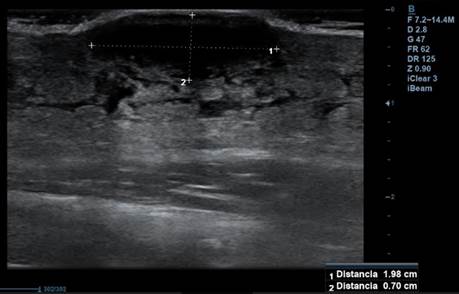

En la consulta se hace una ecografía de partes blandas en la que se observa contenido hipoecoico de 0,7 x 0,9 cm sin restos de detritus. Se inicia tratamiento antibiótico con cloxacilina y se cita para revisión en 3 días. En la consulta de revisión, se objetiva mejoría parcial de la lesión, pero continúa con cierto grado de inflamación. Se repite ecografía (figura 2) y se ve que persiste zona hipoecoica de 1,98 x 0,7 cm, por lo que se hace drenaje de la zona, con salida de restos hemáticos, pero no de material purulento ni de detritus.